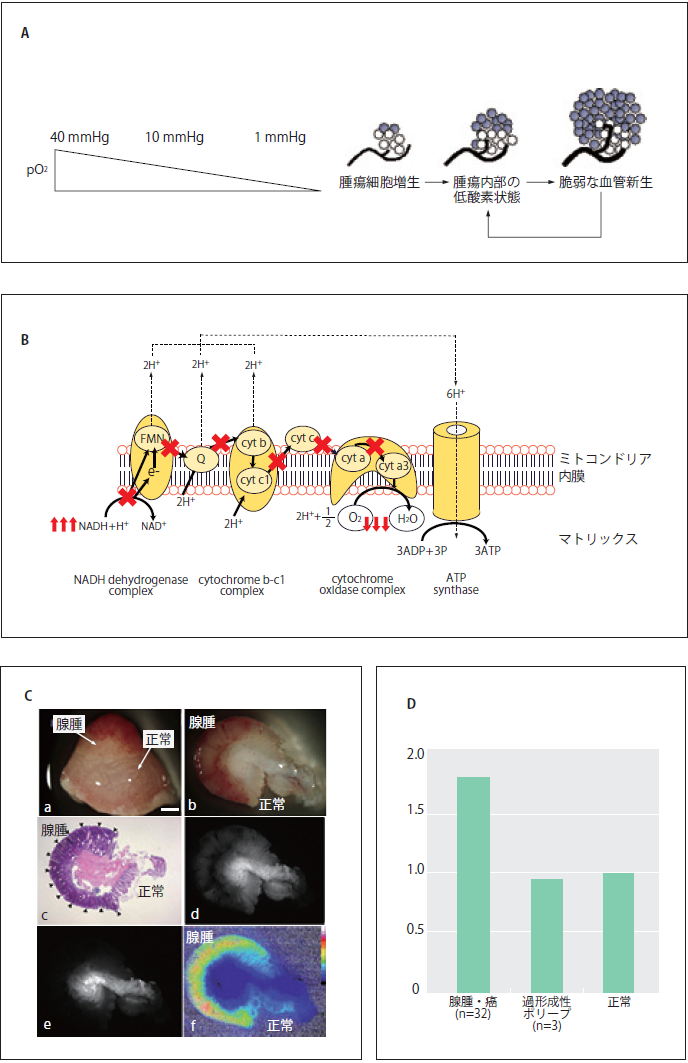

2)生体に内在する蛍光を用いた微小大腸腫瘍の検出

現在臨床において使われている内視鏡は大腸腫瘍の検出に有効であるが、主に形態的変化に基づき診断を行うため、形態変化の小さな微小腫瘍や平坦型腫瘍に対して十分な感度を持っているとは言えない5)。大腸内視鏡検査が形態変化の小さな腫瘍を見逃す頻度は高く、直径5~10mm、1~5mmの腺腫に対する見逃し率は、それぞれ13%、26%といわれている6)。我々は、形態変化に着目するよりも腫瘍化に伴う代謝変化に着目することが、内視鏡の診断能を上げるために有効と考えた。腫瘍は初期段階から代謝変化を伴い、また一般的に固形腫瘍は低酸素状態にあることが知られている7)。生体には数種類の内在性蛍光物質が含まれており、特にnicotinamide adenine dinucleotide (NADH)は細胞代謝に関連して蛍光強度が変化し、細胞が低酸素状態に陥るとNADH蛍光強度は上昇することが知られている8)。大腸癌の発生母地である大腸粘膜はNADHを豊富に含むため9)、大腸粘膜の腫瘍化をNADH蛍光強度の違いとして捉えられる可能性がある。ただ、生体内においてNADH蛍光を正確に測定するには、ヘモグロビンはNADHの励起光・蛍光を強く吸収するため、血液の影響を軽減・除去する必要がある。最近我々は、血液ヘモグロビンの光吸収の影響を除去可能な2波長励起蛍光イメージング法を開発し、ヒト大腸腺腫切除検体を用いてその高い診断能を報告した10)11)。2波長励起蛍光イメージング法は、NADH蛍光光量が最大となる波長を含むイメージ(Excitation:365nm)およびレファランス蛍光イメージ(Excitation:405nm)をそれぞれ取得後、画像間レシオ演算を行うことにより、腫瘍の血管密度や形状の影響の少ない腫瘍イメージングが可能な方法である(図2C,D)。すなわち、内視鏡的粘膜切除術を施行された大きさ3 mm以下のヒト大腸腺腫も高いS/N比で描出でき、in vivo においてラット微小大腸癌を検出可能であった。同方法は、蛍光レシオを擬似カラーとして表示する内視鏡システムを作製することにより比較的簡便に臨床応用可能であり、微小腫瘍の内視鏡的検出に有望である。

図2 生体内在性蛍光を用いたヒト大腸腺腫イメージング

A) 低酸素環境は固形腫瘍に共通した特徴である。がん組織はその発生初期から微小循環動態の欠陥等により恒常的に 低酸素状態にあるといわれている(J. Bull Cancer 2006;93:E73-80)。 B) ミトコンドリア呼吸鎖の模式図。細胞が 低酸素環境にさらされると細胞内NAD+/NADH redox状態は変化し、蛍光を持つNADHが増える。C) ヒト大腸腺腫 イメージング[a: 表面像(白色光)、b: 断面像(白色光)、c: 断面像(HE)、d: 断面像(NADH蛍光)、e: 断面像(レファレンス蛍光)、 f: 断面像(2波長励起蛍光イメージ:レシオ画像=NADH蛍光/レファレンス蛍光)]。2波長励起蛍光イメージング法を用いる ことにより、腫瘍の血管密度や形状の影響を受けない大腸腺腫イメージングが可能(C, D)。Scale bar = 1 mm